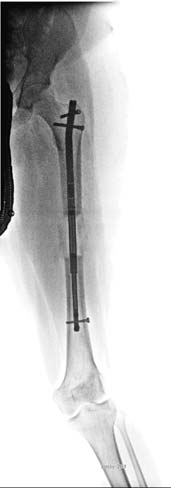

帕利等人(2013年)进行了一项回顾性单中心研究,基于某单一中心三位外科医生的经验[19]报告PRECICE系统的早期结果。本研究已获得机构审查委员会批准。结果首次于2013年4月在希腊雅典举行的欧洲小儿骨科学会年会上发表,随后在加拿大多伦多的北美小儿骨科学会(POSNA)上发表。该研究最近已发表[20]。作者回顾了2011年12月1日至2012年12月4日期间植入的48例连续患者(65个PRECICE钉)的结果(均为PRECICE 1)。本系列患者的平均年龄为25.6岁(10.3–58.4岁)。23名患者因先天性不等长(FIGURE 5)进行了延长;平均年龄为18.5岁(10.3–43.7岁),术前平均延长目标为4.91厘米(1.5–6.5厘米),而术前平均下肢长度差异为6.27厘米(1.5–18.2厘米)。延长速率为0.8毫米/天。除五名患者外,该组所有患者均达到了延长目标;平均延长长度为4.5厘米(0.5–6.5厘米)(FIGURES 6& 7)。四名患者因发育性不等长进行了延长;平均年龄为17.8岁(13–27岁),术前平均延长目标为3.68厘米(1.5–6.5厘米)。延长速率为1毫米/天。平均延长长度为3.68厘米(1.5–6.5厘米)。所有患者均无并发症地实现了术前延长目标。六名患者因创伤后肢体长度差异(FIGURE 8)进行了延长;术前平均目标为3.48厘米(1.7–5.0厘米),平均年龄为

术前前后位和侧位X光片 (B) 使用10.7毫米大转子入路PRECICE 1胫骨钉进行6.5厘米延长后的前后位和侧位X光片(我们使用了胫骨钉,因为在当时大转子入路股骨钉尚不可用;目前的P2胫骨钉磁铁较短,不适合使用,但P1胫骨钉具有常规长度的磁铁,可用于股骨)。这是我们在2011年12月完成的首例PRECICE手术。(C) 6.5厘米延长后显示加重的外翻畸形的前后位X光片。(D) 通过内侧闭合楔形截骨术并使用锁定钢板内固定对畸形进行急性矫正后的前后位和侧位X光片。同时行腓神经减压术以尽量减少神经牵拉损伤的风险。(E) 一年后所有植入物取出后的最终前后位和侧位X光片。)